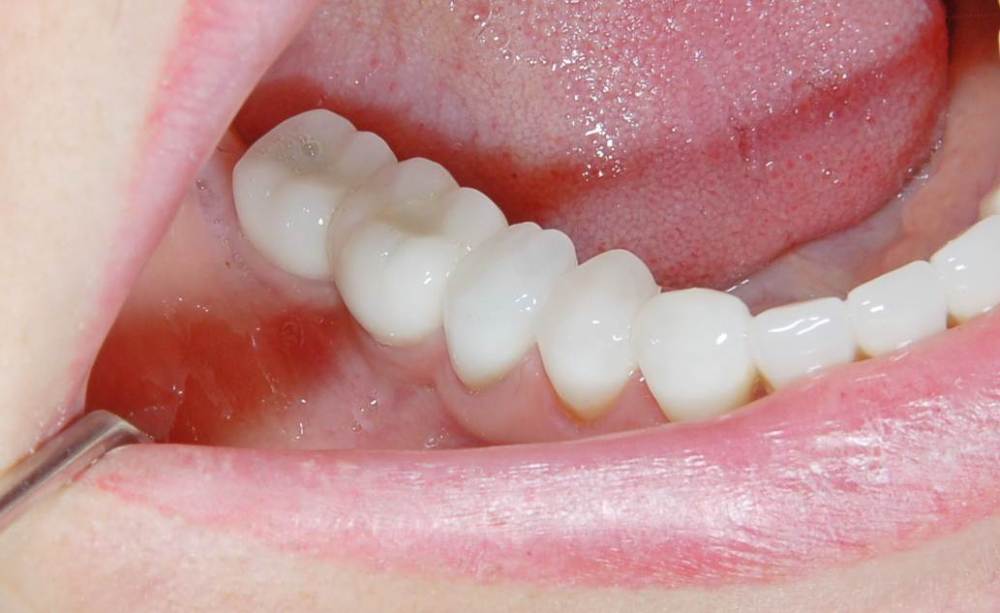

Большой Зеленый Опубликовано 7 ноября, 2022 Поделиться Опубликовано 7 ноября, 2022 Обратите внимание на даты 2 Ссылка на комментарий

Большой Зеленый Опубликовано 7 ноября, 2022 Поделиться Опубликовано 7 ноября, 2022 У дилера есть премил абатменты. За 10 лет работы проблем никаких не было. 1 Ссылка на комментарий